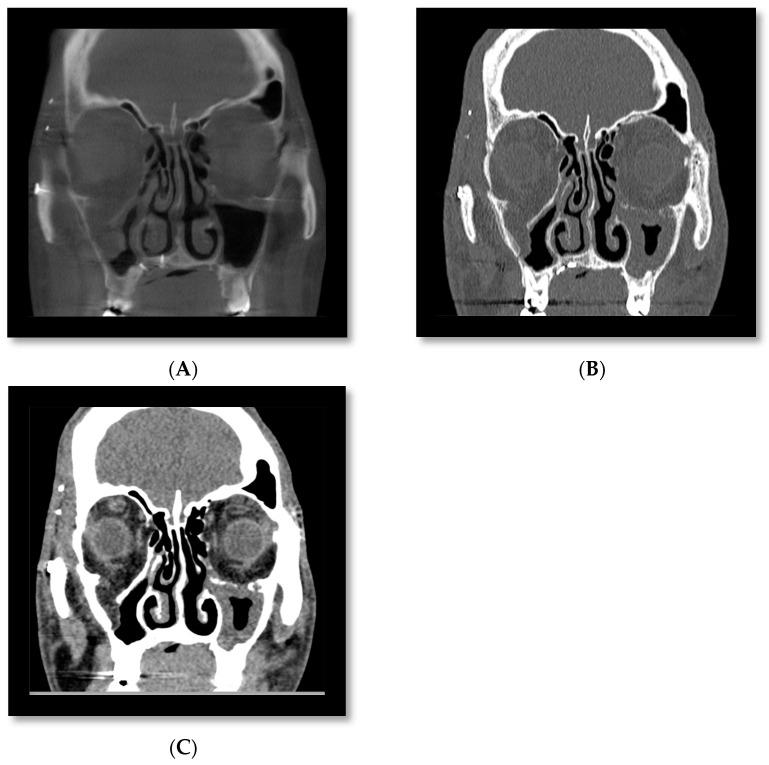

The assessment and management of facial trauma in an acute setting is one of the core services provided by oral and maxillofacial units in the United Kingdom. Imaging is a pre-requisite for appropriate diagnosis and treatment planning, with a combination of plain radiographs and medical-grade CT being the mainstay. However, the emergence of cone beam CT in recent years has led to its wider applications, including facial trauma assessment. It can offer multi-planar reformats and three-dimensional reconstruction at a much lower radiation dose and financial cost than conventional CT. The purpose of this review is to appraise its potential indications in all anatomical areas of maxillofacial trauma and provide our experience at a level 1 trauma centre.

在急性情况下对面部创伤进行评估和处理是英国口腔颌面科室提供的核心服务之一。影像学检查是进行恰当诊断和治疗规划的先决条件,主要依靠普通X光片和医用级CT的联合使用。然而,近年来锥形束CT的出现使其得到了更广泛的应用,包括面部创伤评估。与传统CT相比,它能够以更低的辐射剂量和经济成本提供多平面重建和三维重建。这篇综述的目的是评估其在颌面创伤所有解剖区域的潜在适应证,并介绍我们在一级创伤中心的经验。